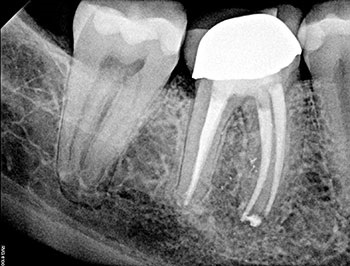

After the buildup and root-filling material were removed, a microscope was used to confirm that no cracks were present in the pulp chamber or the coronal third of the canals. This tooth was treated in multiple visits using calcium hydroxide, an antimicrobial intracanal medicament, and to confirm healing. The root canal system was cleaned, calcium hydroxide was placed, and a double-layered long-term provisional restoration made of Cavit and bonded composite were placed to seal the access preparation.

The patient returned in three months, when resolution of symptoms, healing of the deep probing defect and bone regeneration were confirmed. The tooth was obturated, and a foundational restoration was placed before the rubber dam was removed. Fourteen years of follow-up confirmed long-term periradicular health. The amount of appreciation and gratitude that this patient expressed reminds us that each individual tooth demands our best efforts.

Fig. 2: Postoperative PA.